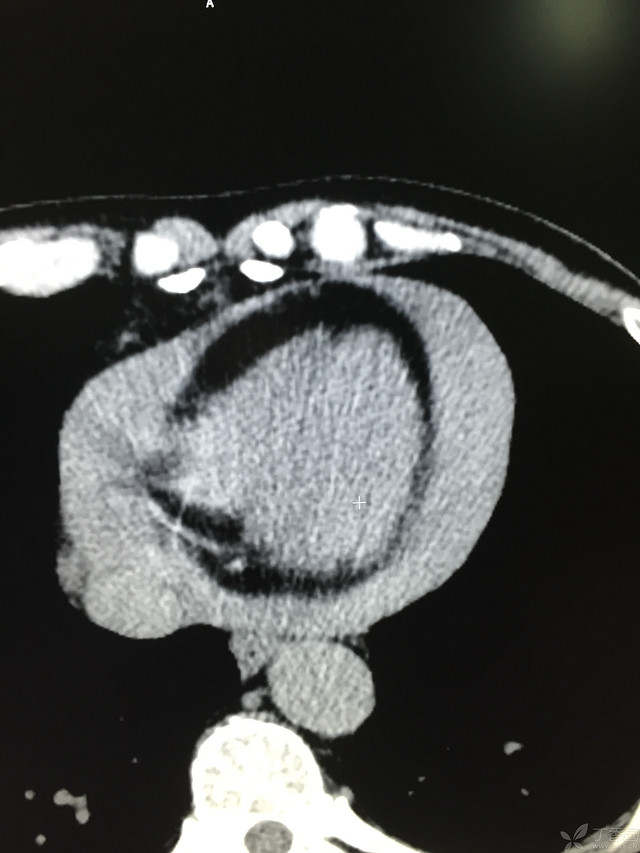

胸痛三天,加重三小时(CT是心包高密度影是什么)

患者性别:男

患者年龄:64岁

简要病史:三天前休息时突发胸前区疼痛伴大汗,到当地医院输液治疗后缓解,3小时前情绪激动后再次出现胸痛伴大汗,胸部压迫感,持续不缓解入院,到当地医院测血压180/?mmHg泵入硝酸甘油转入我院。

体格检查:血压94/72mmHg(右侧)96/74mmHg(左侧),心率78此/分,其他未见阳性体征